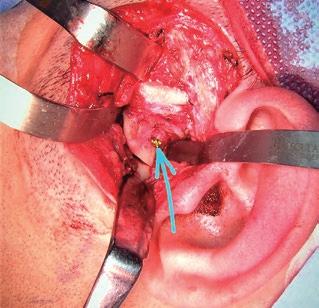

una discectomía asociada. Sus ventajas son su sencillez, su bajo índice de complicaciones y su acceso casi directo a la cápsula de la ATM. Sus inconvenientes son las cicatrices, visibles siempre; su exposición limitada, sobre todo en la parte más inferior, que por otra parte es la más necesaria en las fracturas, y el potencial daño nervioso a las ramas motoras del nervio facial o las sensitivas del nervio aurículotemporal. Además, suele ser necesario ligar los vasos temporales superficiales que siempre aparecen durante la disección. Está indicada en fracturas condilares altas (cabeza o cuello) o cuando el cóndilo se encuentra muy desplazado y dislocado medialmente. Se puede combinar con una extensión temporal de Al-Kayat cuando se necesita un mayor campo quirúrgico (sobre todo en la zona anterior) y para minimizar el daño a la rama frontal del nervio facial (fig. 2).

SFIG. 2, a-i. Fractura subcondilar izquierda baja consolidada en una posición incorrecta y que requirió una nueva cirugía abierta correctora a través de una incisión preauricular con descarga. a) Detalle de la OPG con el eje mayor normal condilar (línea verde) el eje mayor del cóndilo desplazado (línea roja) con la línea de fractura (línea azul) y más de 30o de desplazamiento antero-medial. b) Diseño de la incisión preauricular con la descarga temporal de Al-Kayat (negro) y dibujo aproximado de las estructuras óseas anatómicas (azul). c) Apertura de la fascia temporal superficial con electrobisturí y punta de Colorado a 45o para evitar dañar durante la disección la rama frontal del nervio facial; se observa los vasos temporales superficiales ligados (flechas azules). d) Exposición de la fractura con el cóndilo mandibular (C) visto desde su cara posterior al estar desplazado y rotado ántero-medialmente fuera de la fosa glenoidea (F) por delante de la eminencia temporal (E), estando el disco articular (D) bien posicionado, por lo cual no se abre el espacio articular superior. e) Imagen durante la refractura del cóndilo mal posicionado mediante una sierra mecánica reciprocante (S), protegiendo por medial la arteria maxilar interna con una valva maleable (V) posterior para no dañarla y con un periostótomo angulado (P) anterior. f) Tras la osteotomía se coloca un tornillo (flecha azul) de 2 mm a medio insertar en la cara posterolateral del cóndilo. g) Mediante una pinza de hueso se tracciona del cóndilo lentamente hacia atrás y hacia abajo (flecha azul) y se reposiciona adecuadamente dentro de la fosa articular, pivotando sobre la línea de fractura (flecha amarilla). h) Imagen tras la adaptación y osteosíntesis de una miniplaca de titanio de 1,5 mm de grosor y 6 tornillos monocorticales para estabilizar el cóndilo manteniendo ya una adecuada oclusión dental. i) Sutura por planos de la herida con monofilamento y colocación de un drenaje aspirativo (arriba) que se mantendrá durante 48 horas.

SFIG. 3, a-e. Fractura subcondilar alta derecha tratada con cirugía abierta y abordaje endaural (pruebas de imagen en la fig. 1). a) Diseño de la incisión endaural a la ATM derecha, escondida tras el trago y con descarga superior en la base del hélix. b) Campo quirúrgico en el abordaje endaural durante la maniobra de reducción del fragmento condilar dislocado antero-medialmente, con lo cual es necesario un movimiento caudal (flechas rojas) y anterior (flechas verdes) de la mandíbula traccionando el asistente con una pinza de ganchos doble (tipo cangrejo) posicionada en el ángulo mandibular (línea negra punteada). c) Durante la maniobra de reducción del fragmento dislocado traccionando de él hacia atrás y haciafuera con una pinza ósea (VO) y del ángulo mandibular con una pinza de cangrejo (PC) para dar obtener más espacio, se infiltra el músculo pterigoideo medial con 25 unidades de toxina botulínica (Tx) empleando una aguja im. larga, con el fin de disminuir la contracción de mismo y mejorar la estabilidad de la fractura durante los siguientes meses. d) Comprobación de la estabilidad de la fractura tras la osteosíntesis con una placa delta de titanio (Modus®, Medartis®, Basel, Switzerland) (flecha amarilla), realizando movimientos mandibulares de apertura y lateralidades. e) Control posoperatorio 1 año tras la cirugía mediante radiografía panorámica donde se aprecia una adecuada posición del cóndilo mandibular en la ATM y la formación del callo óseo (flecha amarilla).